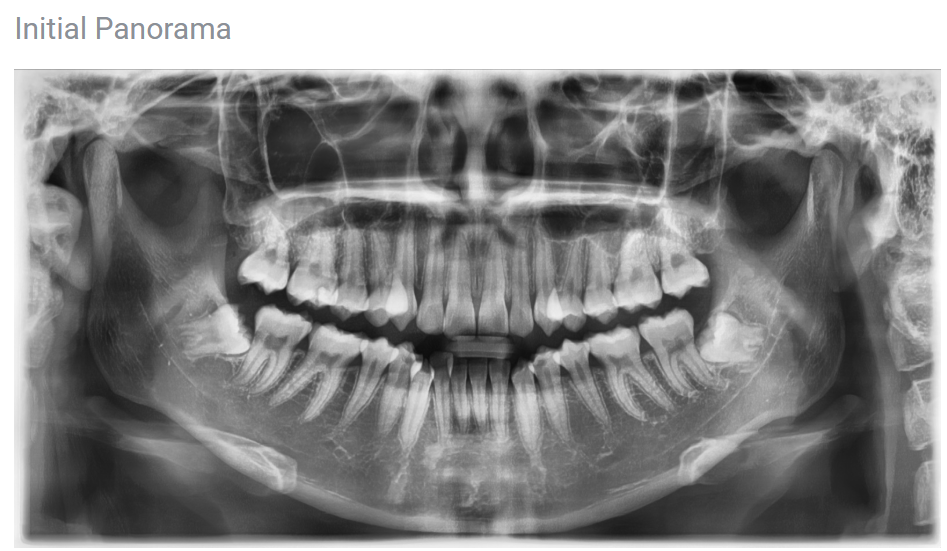

It is essential to make a diagnosis that also looks at the overall facial proportions and tooth alignment through CT scans and dental cast analysis.